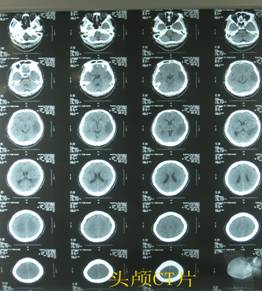

8、医学影像诊断技术

主要内容是各系统正常影像表现,各系统疾病基本影像表现,常见疾病的影像学表现。旨在使员工获得影像诊断的基本理论知识和必要的诊断技能,具有分析解决实际问题的能力。

9、超声诊断技术

主要内容是通过超声成像设备,以声像图显示人体组织和器官断层解剖与病理形态变化;或者进行介入操作,以达到诊断和治疗的目的。旨在使员工获得超声诊断学的基本理论知识和必要的诊断技能,具有分析解决实际问题的能力。